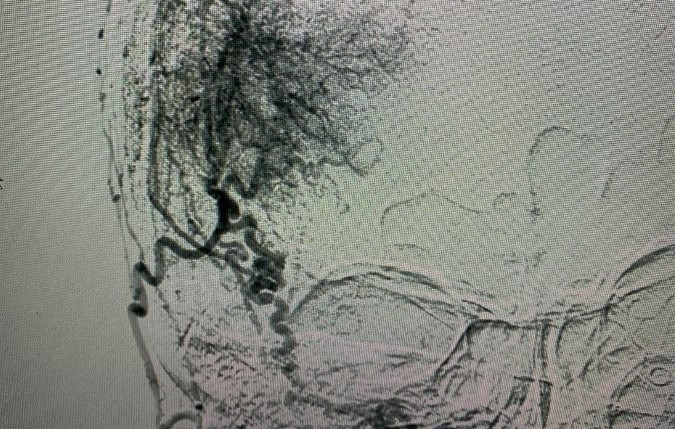

Đau đầu nhiều năm, phát hiện khối u ở não to hơn quả trứng vịt

Người phụ nữ ở TP.HCM mang khối u ở màng não to hơn quả trứng vịt, có rất nhiều mạch máu nuôi.